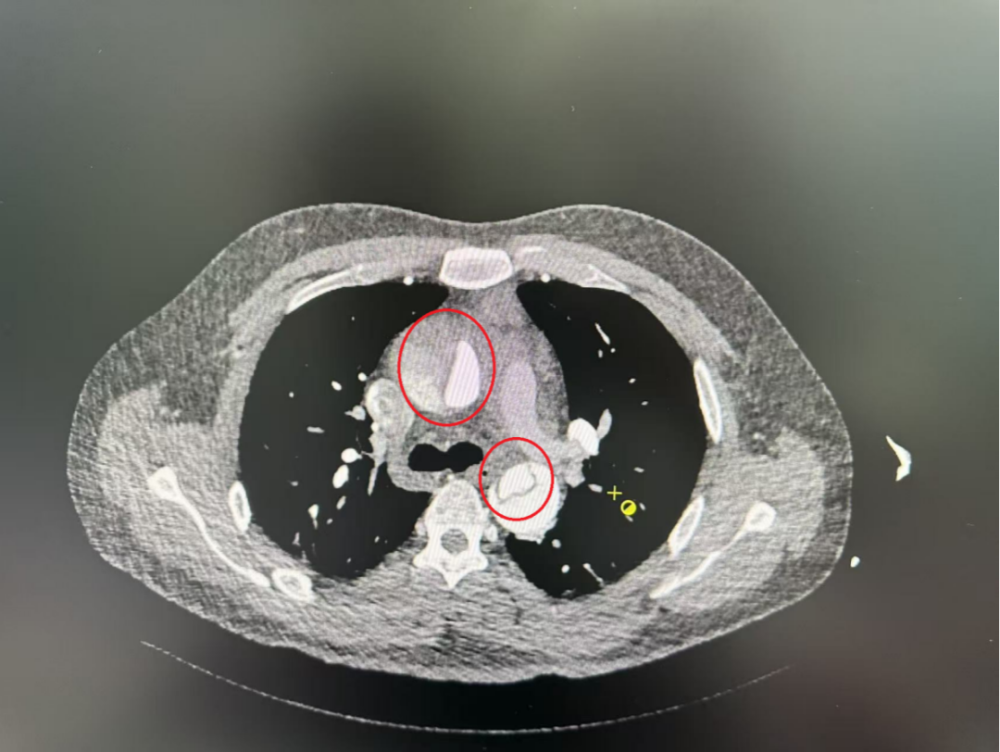

患者CT血管成像

30余岁的小张(化名)凌晨在睡梦中突发胸背部剧烈疼痛,被家人紧急送至交大一附院榆林医院急诊医学科。经询问,患者有高血压病史,最高血压达196/100mmHg,但未规律服药,并长期存在吸烟、饮酒、作息不规律等情况。急诊医生凭借多年临床经验结合患者病史,当即开启绿色通道,紧急请心血管外科医生会诊。在心血管外科医生陪同下,患者完成增强CT血管造影检查,确诊为急性主动脉夹层(Stanford A 型),且夹层已从升主动脉累及至下肢动脉。